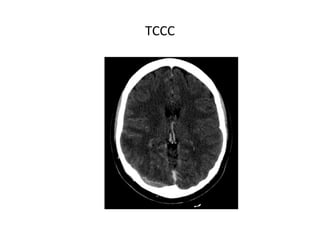

TCCC

SIGNOS INDIRECTOS

- Infartos no hemorrágicos: Frecuentes. (subcortical, sin

distribución arterial típica, proximal al seno afectado).

- Infartos hemorrágicos: 10-50% de los casos, pueden ser

profundos, superficiales o multifocales.

- Edema cerebral difuso.

- Colapso ventricular.

• TC CON CONTRASTE IV

SIGNOS DIRECTOS

- Signo del delta vacío: es el signo directo más frecuente, se

observa hasta en un 30% de los casos.

- Ectasia venosa.

- Realce tentorial.

- Realce giral.

- Realce parenquimatoso.